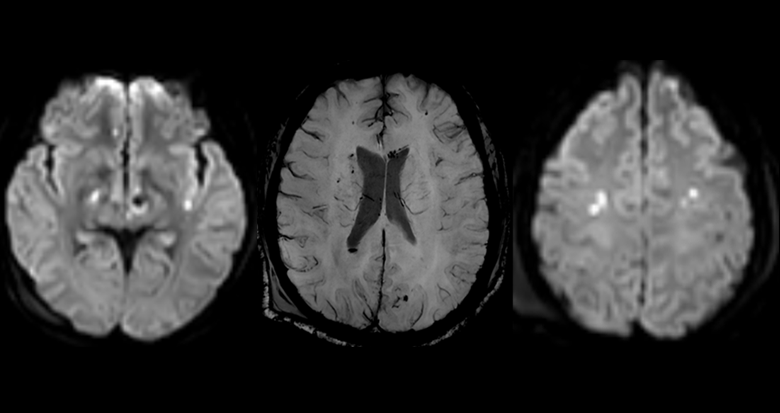

Multiple Lésions punctiformes bilatérales de topographie évocatrice. Examen a visé pronostic à réaliser dans les 7 jours.

Lésion non hémorragiques en Hypersignal T2 -T2 EG : hyposignal des lésions pétéchiales hémorragiques (susceptibilité magnétique). - SWAN/SWI : Imagerie de susceptible magnétique haute résolution. pétechies +++ -Diffusion (+/- Tractographie): Foyers punctiformes en hypersignal diffusion - restriction ADC.